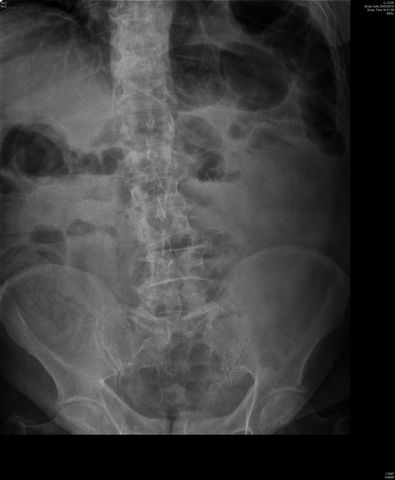

Diverticulosis de colon.